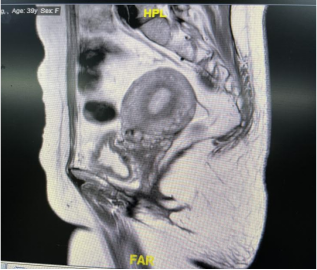

果不其然,张婷的盆腔影像学检查结果提示了很多结构异常。盆腔核磁检查结果显示:膀胱下段与宫颈之间粘连紧密,以前手术放入的网片与双侧三角区关系密切。盆底超声提示尿道旋转角及膀胱后角角度均有明显增大,尿道向后下方移位,但与尿道相连的膀胱上段却并无位置移动;在宫颈前方,7个月前手术放入的网片将子宫颈与膀胱后壁下段紧密粘连。这些信息,成为破解谜团,解除患者痛苦的重要线索。

“膀胱下段粘连固定,尿道却向后下方移位,因此尿道可能形成一定角度,阻碍排尿。”超声科专家耿京根据所见提出了推测。提供的动态超声视频显示,膀胱后壁上段与宫颈粘连固定在一起,并不与其他部位一起运动,这更加支持了该推测。